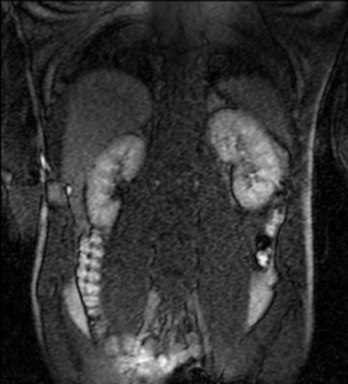

Tables 1 and 2 show our quantitative results: PSNR between the style (image we want to transfer style from) and generated image, SSIM and MS-SSIM between the content (image we want to take structure from) and generated image and finally, our proposed weighted SSIMs. For each style transfer direction and metric, our method consistently outperforms the other approaches. Figures 2 and 3 qualitatively highlight the good results of our method on 2D and 3D datasets. In addition, quantitative results on both figures show that our proposed metric preserves qualitative ordering of results for both style and content. In comparison, metrics such as SSIM struggle to accurately correlate to visual results.

Qualitative evaluation shows that the proposed method leads to sharper images, better content preservation, better localised CE and realistic MRI appearance. Quantitatively, we outperform the other algorithms with each metric, for each style transfer direction. While we expected that adding CE to images would be an easier task than removing CE, we found that for both tasks the method exhibits similarly performing quantitative and qualitative results. The results for style transfer with the kidney data show that when there is clear CE, it is easier to perform style transfer in both directions. However, when style transfer is performed on the prostate data, the model struggles in comparison to the kidney data. This may be due to the enhancement of the prostate being less defined than the kidney data. In figure 3(b), we can see the prostate with CE. Compared to figure 2(b) showing kidneys with CE, it is harder to determine the edges. The two original images shown in figures 3(a) and 3(b) are clear and easy to see some edges of prostate, in other images, it is harder to see the edges of the prostate.

(C) CW-SSIM: 0.61

(S) CW-SSIM: 0.52

(C) CW-SSIM: 0.42

(S) CW-SSIM: 0.19

(C) CW-SSIM: 0.28

(S) CW-SSIM: 0.49

(C) CW-SSIM: 0.92

(S) CW-SSIM: 0.59